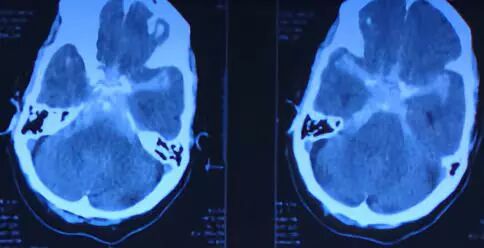

1.男70岁,Fisher 3级,H-H 3级,头CT:SAH。

3.既往高血压病史21年。

造影提示后交通大型动脉瘤,后交通和脉前动脉从瘤体上发出。

大型动脉瘤微导管瘤内成袢超选远端或瘤体上的分支是基本技术。

微导管瘤内解袢是相对应的技术,常用方法是把导丝退到动脉瘤开口以下,旋转导丝,缩小袢,同时下撤微导管,当看到微导管远端头部轻微前跳时说明瘤内袢解开,特殊解袢困难的可采用远端支架或球囊锚定技术。